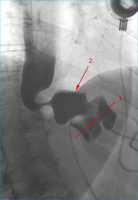

Magenbypass

Abbildung 14: Zustand nach Magenbypass mit Anastomosenleck: a) Zustand nach Anlage eines ersten Stents (1) zur Überdeckung des Lecks, jedoch persistierender, massiver Kontrastmittelaustritt an der gastrojejunalen Anastomose (Pfeilspitze), mit Ausbreitung in den linken Oberbauch; b) überlappende Anlage eines 2. Stents (3) mit nun komplett abgedecktem Leck und unbehinderter Passage. Blindes Ende der Roux-Schlinge (2).

Keywords: GastroenterologieMagenbypassRadiologie